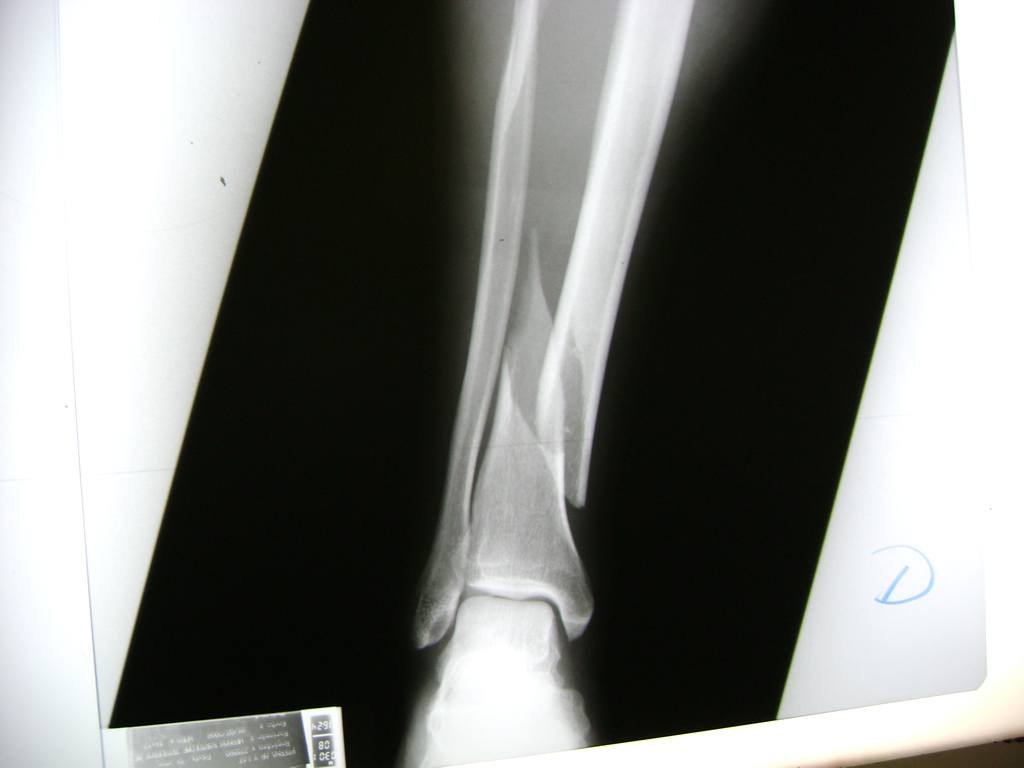

Cirugía de Tibia y Peroné

Aunque cada uno de estos huesos puede fracturarse por separado, normalmente la rotura es una lesión que se produce de forma conjunta

La mayor parte de las roturas implican a la parte proximal del hueso (parte del hueso próximo a la rodilla) o a la parte distal (parte del hueso cerca del tobillo).

Debido a la fina cobertura de piel que recubre la tibia y el peroné, las fracturas generalmente son abiertas, es decir, el hueso roto rasga la piel, atravesándola. Las fracturas de tibia y peroné generalmente se producen por un fuerte impacto o torsión.